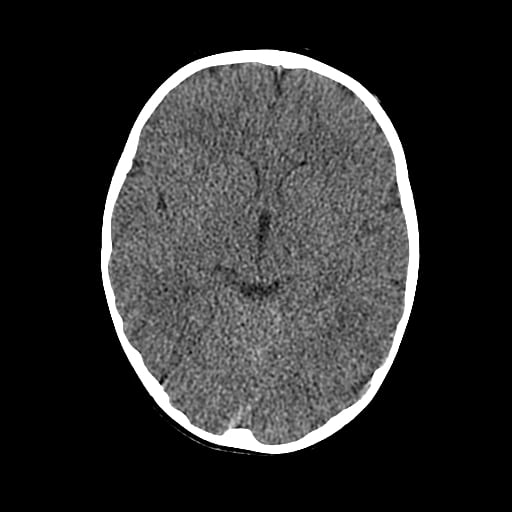

Age: 1

Sex: Male

Indication: Fall